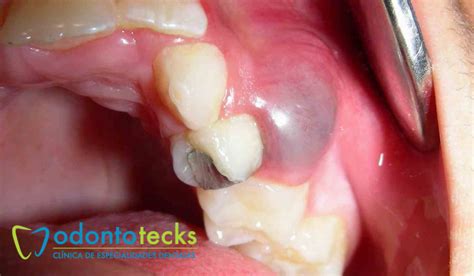

- Puede aparecer una protuberancia semiblanda en la encía cuyo interior está formado por pus.

Cuando un quiste es pequeño y no está infectado, típicamente no duele ni inflama. A medida que aumenta de tamaño, puede empezar a causar presión en el hueso y en los dientes vecinos. A veces notarás un bultito indoloro en la encía o una sensación extraña.

- La encía comienza a presentar dolor e inflamación localizada y pueden aparecer llagas en la zona.